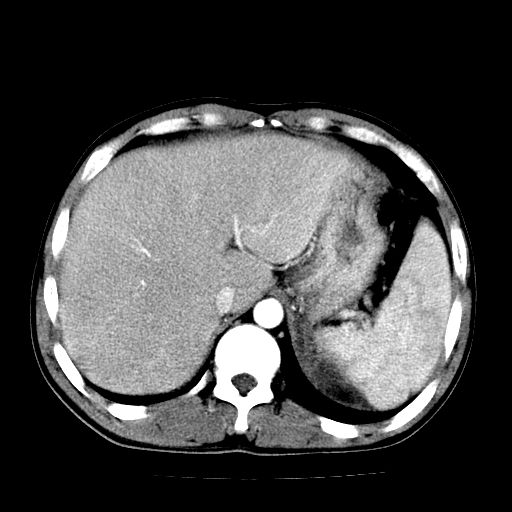

以下是引用天南地北在2007-4-30 13:36:00的发言:[br]支持慢性胰腺炎伴有假性囊肿

以下是引用andymaomao在2007-4-30 14:28:00的发言:[br]支持:1.慢性胰腺炎并假性囊肿形成可能;[br] 2.左肾形态稍增大,旋转不良。